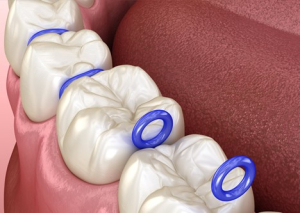

جدا کننده های ارتودنسی (که معمولاً به عنوان اسپیسر یا سپراتور شناخته می شوند) رابر بندها یا ابزارهای فلزی هستند که در ارتودنسی استفاده می شوند. سپراتورها در جلسه دوم ارتودنسی، قبل از اعمال بندهای دندان های مولر، بین دندان های مولر قرار داده می شوند. اسپیسرها یا رابر بندهای دایره ای به قطر حدود یک سانتی متر هستند که بین دندان های مولر بالا و پایین قرار می گیرند. ممکن است 1 تا 8 اسپیسر وجود داشته باشند یا گیره های فنری فلزی کوچک (جدا کننده های فنری) که دندان های مولر را از هم جدا می کنند. فاصله دهنده ها به مدت یک تا دو هفته بین دندان ها باقی می مانند و دندان ها را به آرامی از هم دور می کنند تا زمانی که به اندازه کافی از هم فاصله بگیرند تا ارتودنتیست ها بتوانند بریس های دندان ها یا بندهای دندان های مولر را بین آنها قرار دهند یا یک اکسپندر با حلقه های فلزی قرار دهند.

فرآیند قرار گیری اسپیسرها بین دندان ها معمولاً شامل کشیدن نخ دندانی است که از داخل سپراتور عبور داده شده است و قرار دادن سپراتور بین دندان ها است. برخی از اسپیسرها گیره های فنری فلزی کوچکی هستند که دندان ها را از هم جدا می کنند. در طول فرآیند مقداری فشار و بعد از آن مقداری درد وجود دارد، اما به طور کلی، فرآیند استفاده از اسپیسرها کاملاً بدون درد است، اگرچه ممکن است بیمار بلافاصله از فشار وارد شده به دندان ها احساس درد کند. گاهی اوقات بسته به فشردگی دندان ها از ابزارهای مخصوص ارتودنسی برای باز کردن کش ها استفاده می شود. اگر بخصوص دندان های قوس دندانی فشرده باشند، اسپیسرها ممکن است به دلیل نزدیک تر شدن بیشتر دندان ها باعث درد شدید دائمی شوند. این درد مدتی پس از قرار دادن شروع می شود و معمولاً چند روز طول می کشد.